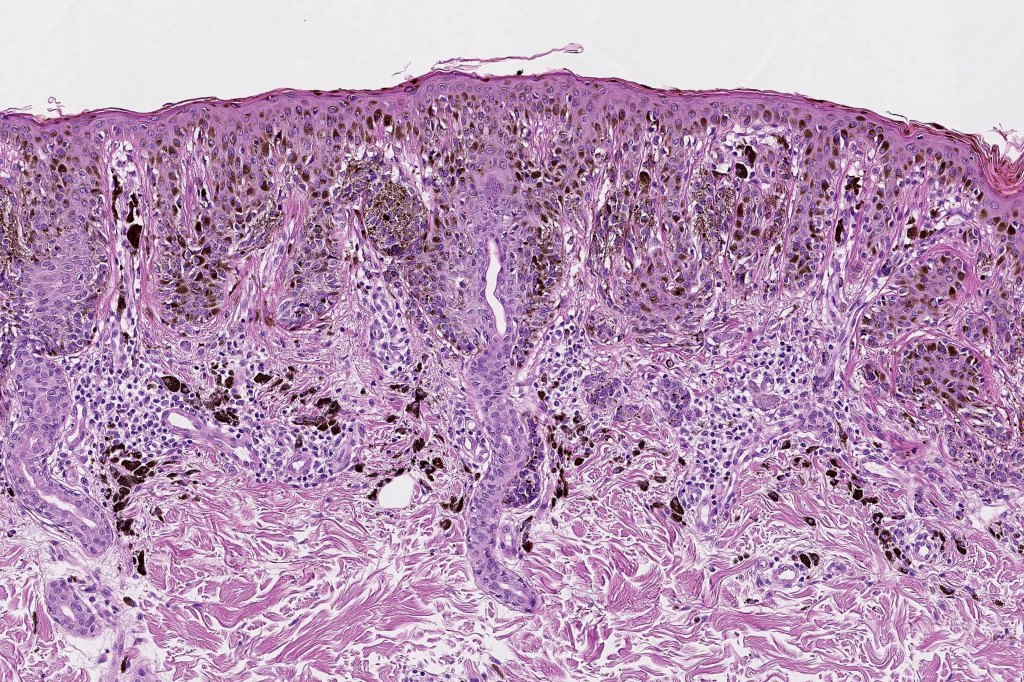

Histological features

•Architectural disorder- lentiginous and nested, nests abnormally located (at the sides of the rete ridges & overlying the dermal papillae in addition to the tips of the rete ridges rather than solely occupying the tips of the rete ridges as is seen in banal nevi), horizontal orientation & bridging between junctional nests (this should not be confused with bridging between adjacent rete ridge squamous epithelium)

•Host response- eosinophilic & lamellar fibroplasia, increased vascularity, lymphocytic infiltration & pigment incontinence